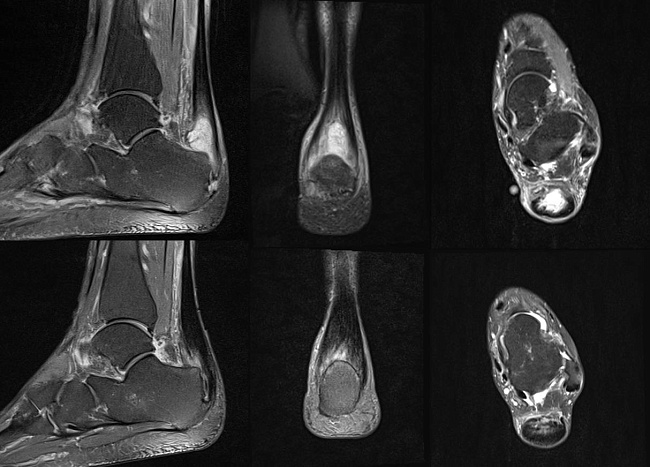

В отчаянии, что эту боль придется терпеть постоянно, женщина обратилась к нам в клинику к травматологу-ортопеду Дедюрину Андрею Анатольевичу. Доктор провел обследование, назначил МРТ и поставил диагноз:

• Основной: инсерционная тендинопатия, субтотальный дегенеративный разрыв левого ахиллова сухожилия.

На контрольной МРТ через 3 месяца сухожилие полностью зажило.